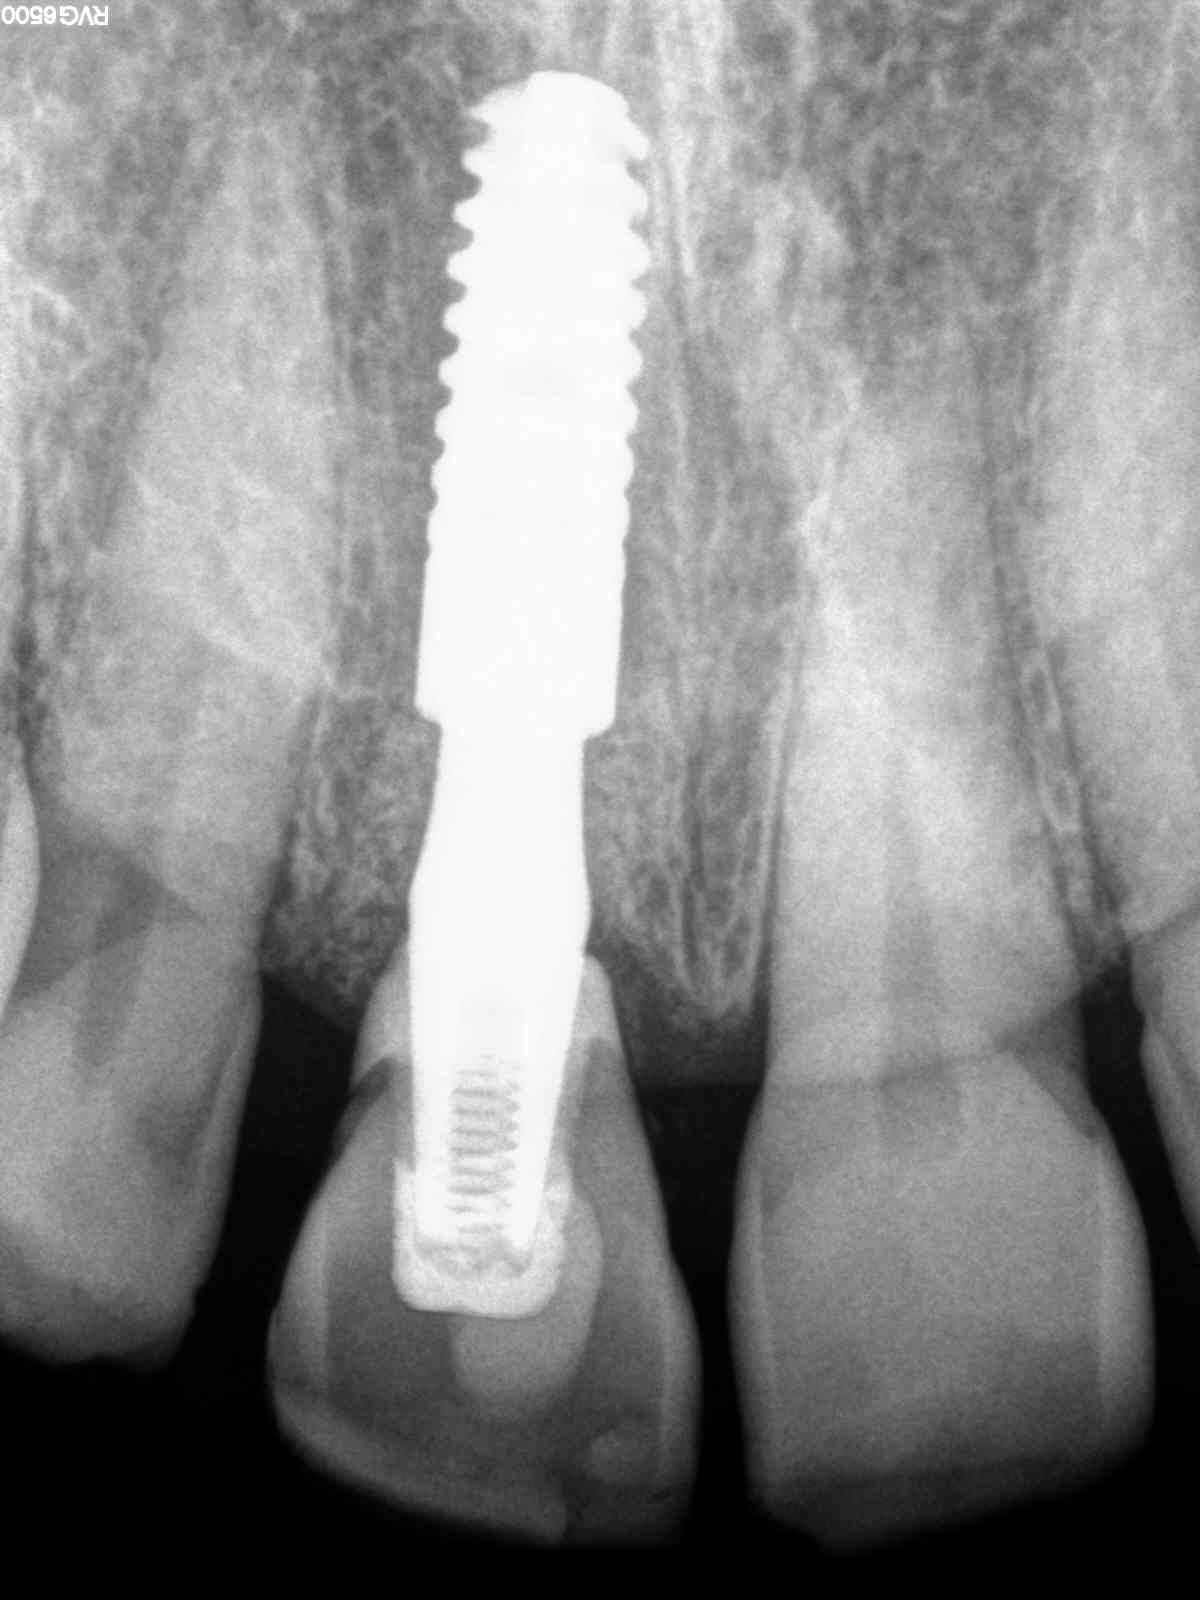

He received his Diploma in Implantology in 2016 from the University of Pretoria, which he passed with Distinction. He is also a member of the International Team for Implantology (ITI), which is based in Switzerland and offers members access to the latest research and cutting-edge techniques.